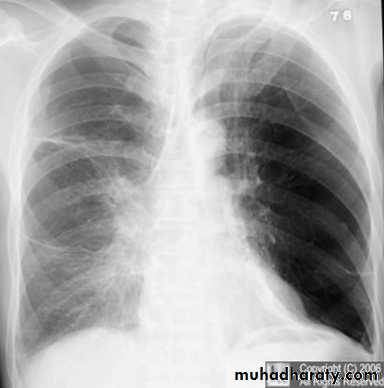

Tension pneumothorax.

On a posteroanterior chest x-ray (A), the left hemithorax is very dark or lucent because the left lung has collapsed completely (white arrows).

The tension pneumothorax can be identified because the mediastinal contents, including the heart, are shifted toward the right, and the left hemidiaphragm is flattened and depressed. A computed tomography scan done on a different patient with a tension pneumothorax (B) shows a completely collapsed right lung (arrows) and shift of the mediastinal contents to the left.